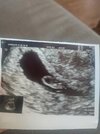

no to super, gratuluję. Nie wiem, od czego zależy kształt pecherzyka i jakie to niesie komplikacje, ale oby to nie było nic takiego.Hej jestem po wizycie. 6+5 zarodek ma 7 mm. Serce bije 110 uderzeń. Brak krwiaków. Jedyne co mu się nie podoba to pęcherzyk z jednej perspektywy wygląda dość płasko. Z innej lepiej. Czekamy. Wizyta za 2 tyg.

a jakie moga byc powody i nastepstwa tego, ze pecherzyk jest bardziej plaski niz powinien?Hej jestem po wizycie. 6+5 zarodek ma 7 mm. Serce bije 110 uderzeń. Brak krwiaków. Jedyne co mu się nie podoba to pęcherzyk z jednej perspektywy wygląda dość płasko. Z innej lepiej. Czekamy. Wizyta za 2 tyg.

GratulujęHej jestem po wizycie. 6+5 zarodek ma 7 mm. Serce bije 110 uderzeń. Brak krwiaków. Jedyne co mu się nie podoba to pęcherzyk z jednej perspektywy wygląda dość płasko. Z innej lepiej. Czekamy. Wizyta za 2 tyg.

kiedyś miałam zły pęcherzyk ale nie było jeszcze nawet zarodka to faktycznie się zapadł i nic z tego nie było. Nie wiem jakie są powody następstwem jest raczej zły rozwój zarodka i w końcu poronienie. Ale on wyglądał dziwnie tylko z jednej perspektywy. Z drugiej jakby lepieja jakie moga byc powody i nastepstwa tego, ze pecherzyk jest bardziej plaski niz powinien?

rozumiem, no to jestesmy dobrej mysli, ze za 2 tyg wyjasni sie, ze wszystko jest okkiedyś miałam zły pęcherzyk ale nie było jeszcze nawet zarodka to faktycznie się zapadł i nic z tego nie było. Nie wiem jakie są powody następstwem jest raczej zły rozwój zarodka i w końcu poronienie. Ale on wyglądał dziwnie tylko z jednej perspektywy. Z drugiej jakby lepiej

rzeczywiście, mój jest całkiem okrągły, jak bank! mydlana, pani dr mowila, jak hyl jeszcze pusty, ze jest i ma ladny, okragly ksztalt, ro dobrze. Mam nadzieję, że to nie jest nic złego i wszystko będzie ok, tym bardziej, że od drugiej strony wyglada ladnie.Widzicie. Z tej perspektywy jest płaski i podłużny.